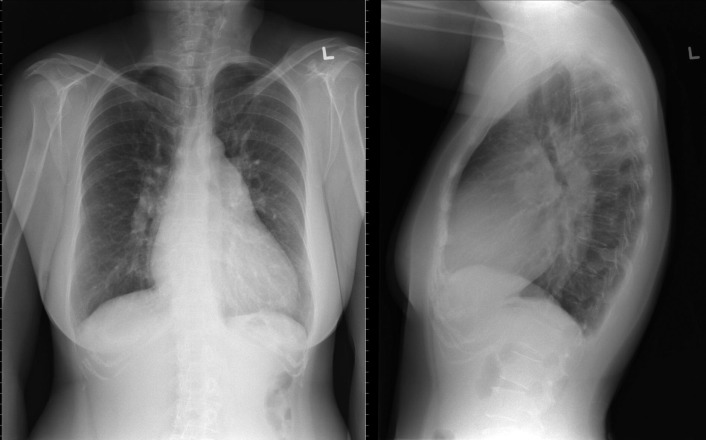

A patent foramen ovale is present in 25% to 30% of the adult population ( Figs. 18-1 to 18-4 ). Any magnitude of shunting across it in normal circumstances is undetectable radiographically. Percutaneous patent foramen ovale closure devices are fairly commonly inserted and are radiographically evident.